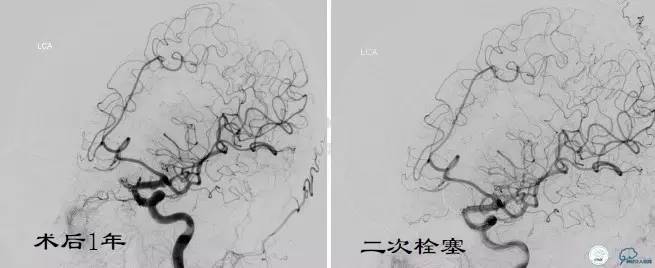

Case3 左ICA床突旁动脉瘤术后复发

术前VS术后即刻